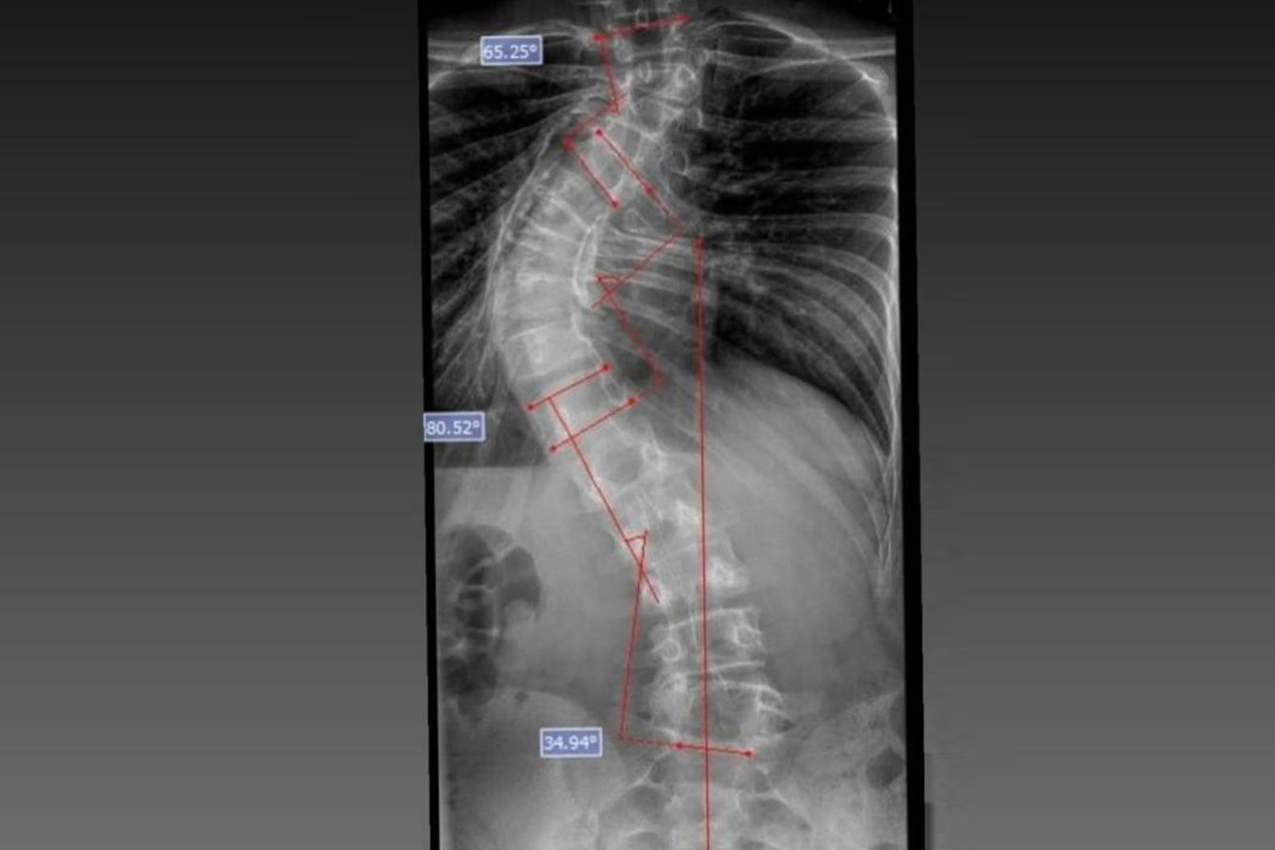

Laura era portadora de escoliose e, em agosto de 2025, realizou a cirurgia de correção da coluna, o que lhe permitirá ter uma vida normal de agora em diante. Moradora de Bom Sucesso do Sul, região Oeste do Paraná, é acostumada a andar a cavalo, mas com o problema na coluna a prática estava longe de ser prazerosa.

A cirurgia ocorreu no dia 28 de julho e uma segunda etapa em quatro de agosto. Desde então, Joyce viu a sua vida mudar. “Nasci com a escoliose e tinha muita dificuldade e limitações para caminhar e perda de movimento. Havia dias em que eu não levantava da cama. Quando saia de casa recebia olhares de julgamento das pessoas, que era o que mais me incomodava. Depois da cirurgia, posso dizer que eu tenho uma nova vida. Eu venci a batalha”, relatou.

O médico João Elias explica que a escoliose é um termo usado para quando você olha a coluna e percebe uma curvatura. Pode acontecer por várias causas, desde uma escoliose congênita, quando o bebê nasce com uma vértebra mal formada e essa vértebra vai levando ao desenvolvimento de uma deformidade na coluna; a neuromuscular, causadas por doenças neurológicas ou musculares, como uma paralisia cerebral, até as idiopáticas, causadas por alterações genéticas e que podem se desenvolver apenas na adolescência.

Segundo ele, o verão é o período em que mais se diagnostica a doença. Por causa do uso de roupas mais leves, é mais fácil notar a alteração na coluna. Caso seja percebida alguma alteração, uma avaliação ortopédica deve ser marcada. “O diagnóstico precoce é importante. Quando a gente percebe que a coluna está iniciando uma curvatura é possível controlar essa curva. Fazer o procedimento com uma curvatura menor permite melhores resultados na cirurgia”, explicou.